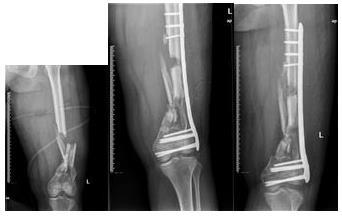

林某 车祸伤致:右侧股骨下段开放性粉碎骨折并10cm骨缺损,左下肢股骨下段粉碎性骨折

右下肢